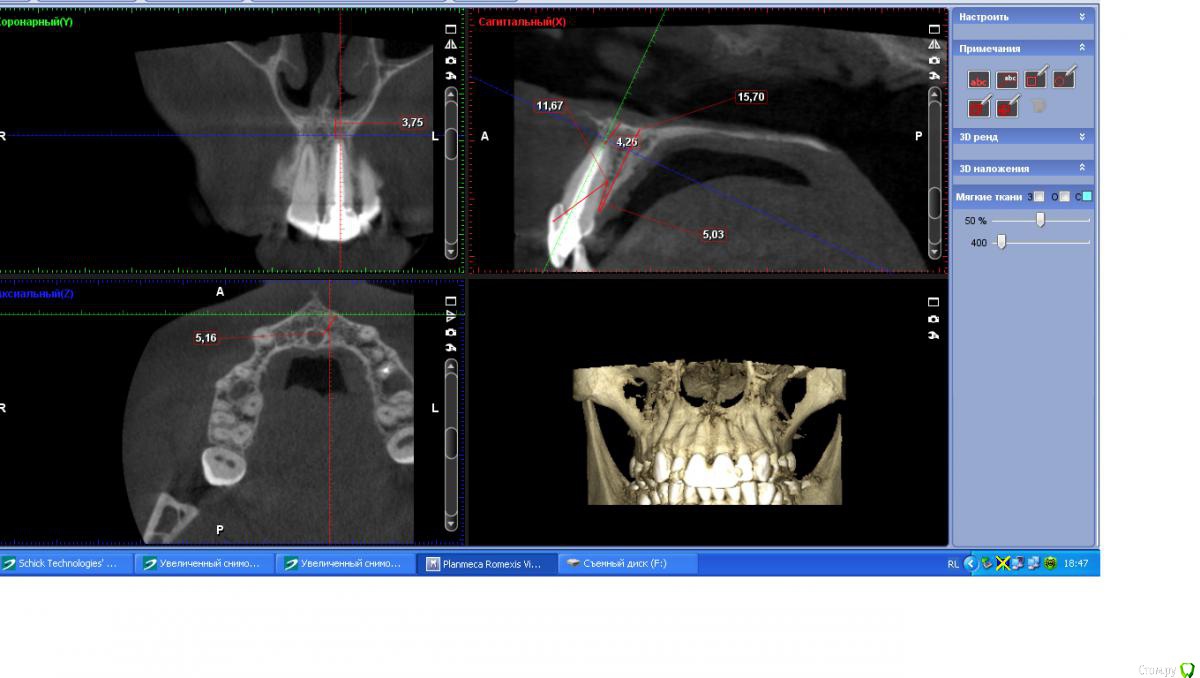

togrul Опубликовано 25 ноября, 2016 Поделиться Опубликовано 25 ноября, 2016 Всем добрый вечер.Сазонова 1.bmpсазонова.bmp 4 Ссылка на комментарий

togrul Опубликовано 25 ноября, 2016 Автор Поделиться Опубликовано 25 ноября, 2016 снимки Ссылка на комментарий

IvanK Опубликовано 26 ноября, 2016 Поделиться Опубликовано 26 ноября, 2016 в идеале, шахта должна выходить в слепую ямку 2 Ссылка на комментарий

Доктор Добрых Дел Опубликовано 26 ноября, 2016 Поделиться Опубликовано 26 ноября, 2016 Края лунки выглядят как будто в ней граната разорвалась. И согласен с коллегами нужно было ещё заглубить и платформу нёбнее немного. Ссылка на комментарий

togrul Опубликовано 26 ноября, 2016 Автор Поделиться Опубликовано 26 ноября, 2016 (изменено) Края лунки выглядят как будто в ней граната разорвалась. И согласен с коллегами нужно было ещё заглубить и платформу нёбе немного.Спасибо за замечание. При удалении пришлось повозиться. Отлично, надо было заглубить. был графт?Да надо было)Да был Лиопласт. Нужно было Bio oss Изменено 26 ноября, 2016 пользователем togrul Ссылка на комментарий

togrul Опубликовано 28 ноября, 2016 Автор Поделиться Опубликовано 28 ноября, 2016 я толком с семадос не знаком, но у них шестигранник и есть болты с фрезерованной шеей. Топикстартер мог бы лучше пояснить. Добрый день. Семадос шестигранное соединение, как мне объяснили имплантат должен быть поставлен на 3 мм от будущего зенита. Для формирования профиля мягких тканей . 1 Ссылка на комментарий